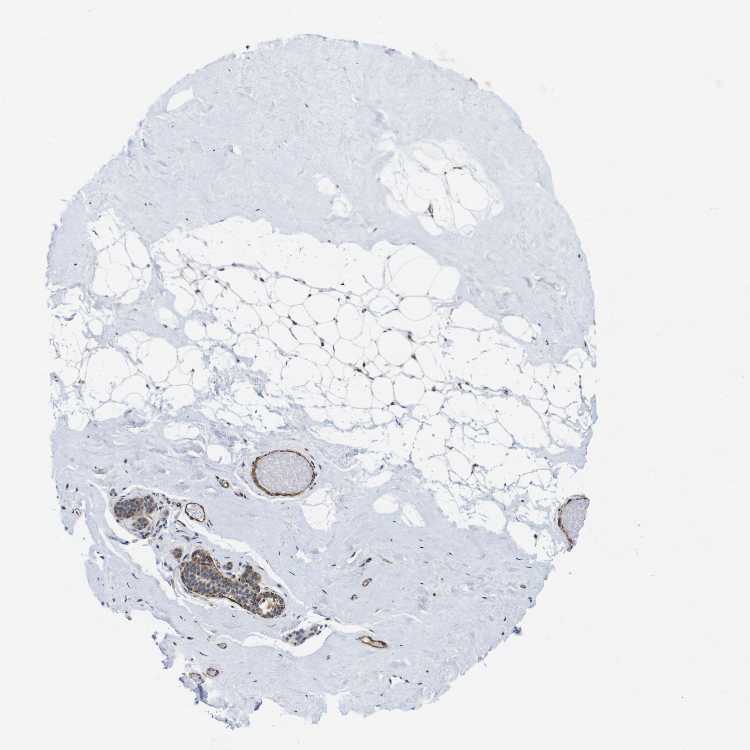

BREAST - Antibody stainingi

Antibody staining in the annotated cell types in the current human tissue is reported as not detected, low, medium, or high, based on conventional immunohistochemistry profiling in selected tissues. This score is based on the combination of the staining intensity and fraction of stained cells.

Each image is clickable and will lead to virtual microscopy that enables deeper exploration of all samples and also displays staining intensity scores, fraction scores and subcellular localization as well as patient and tissue information for each sample.

Antibody HPA013204

Adipocytes Not detected

Glandular cells Low

Myoepithelial cells High